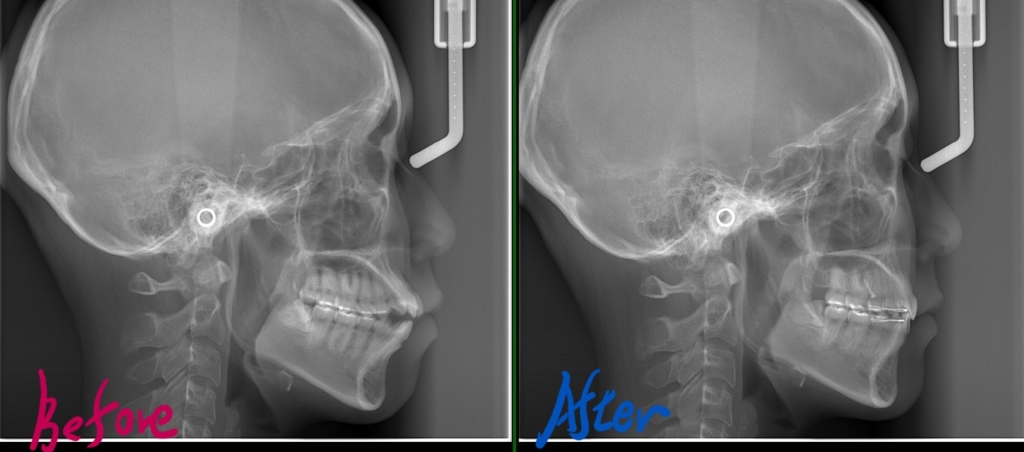

レントゲン写真で確認すると、

【アンカースクリューの使用】 あとは残された隙間を閉じて、奥歯もしっかり噛めるように確立していくステップです。 とりあえず前歯を後方へ動かして引っ込めながら、上顎の奥歯にアンカースクリューを2本植立して補強を加えました。(赤い丸で囲んだ中にあるネジのようなモノがアンカースクリューです)

矯正後の状態をレントゲン写真で確認すると、

アンカースクリューを2本 歯並びがキレイになったことはもちろん、前歯もしっかりと噛めるようになりました。

合わせて、口元や横顔もとてもスッキリさせることができました。 ギリギリ、Eラインに収まったかな。